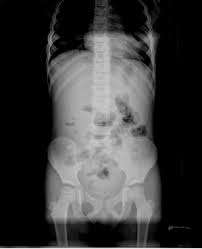

- une radiographie de l’abdomen.